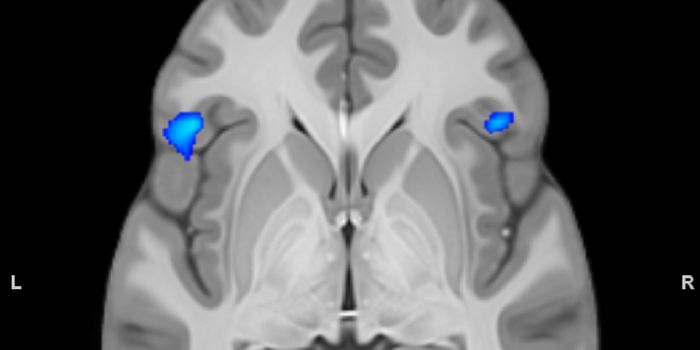

MAY 05, 2020Clinical & Molecular DXImagine a future where we could “see” inside the human brain at stunning high resolution, detecting the earl ...

JUN 28, 2017CancerBrain imaging via MRIs may soon be enhanced with simple sugar instead of conventional metal complexes. A new study found ...

JAN 20, 2022NeuroscienceResearchers focus on the ventral medial prefrtonal cortex as the source of the self

DEC 03, 2020NeuroscienceTo obtain high-resolution images of the brain, researchers usually need to reduce the thickness of the skull or cut into ...